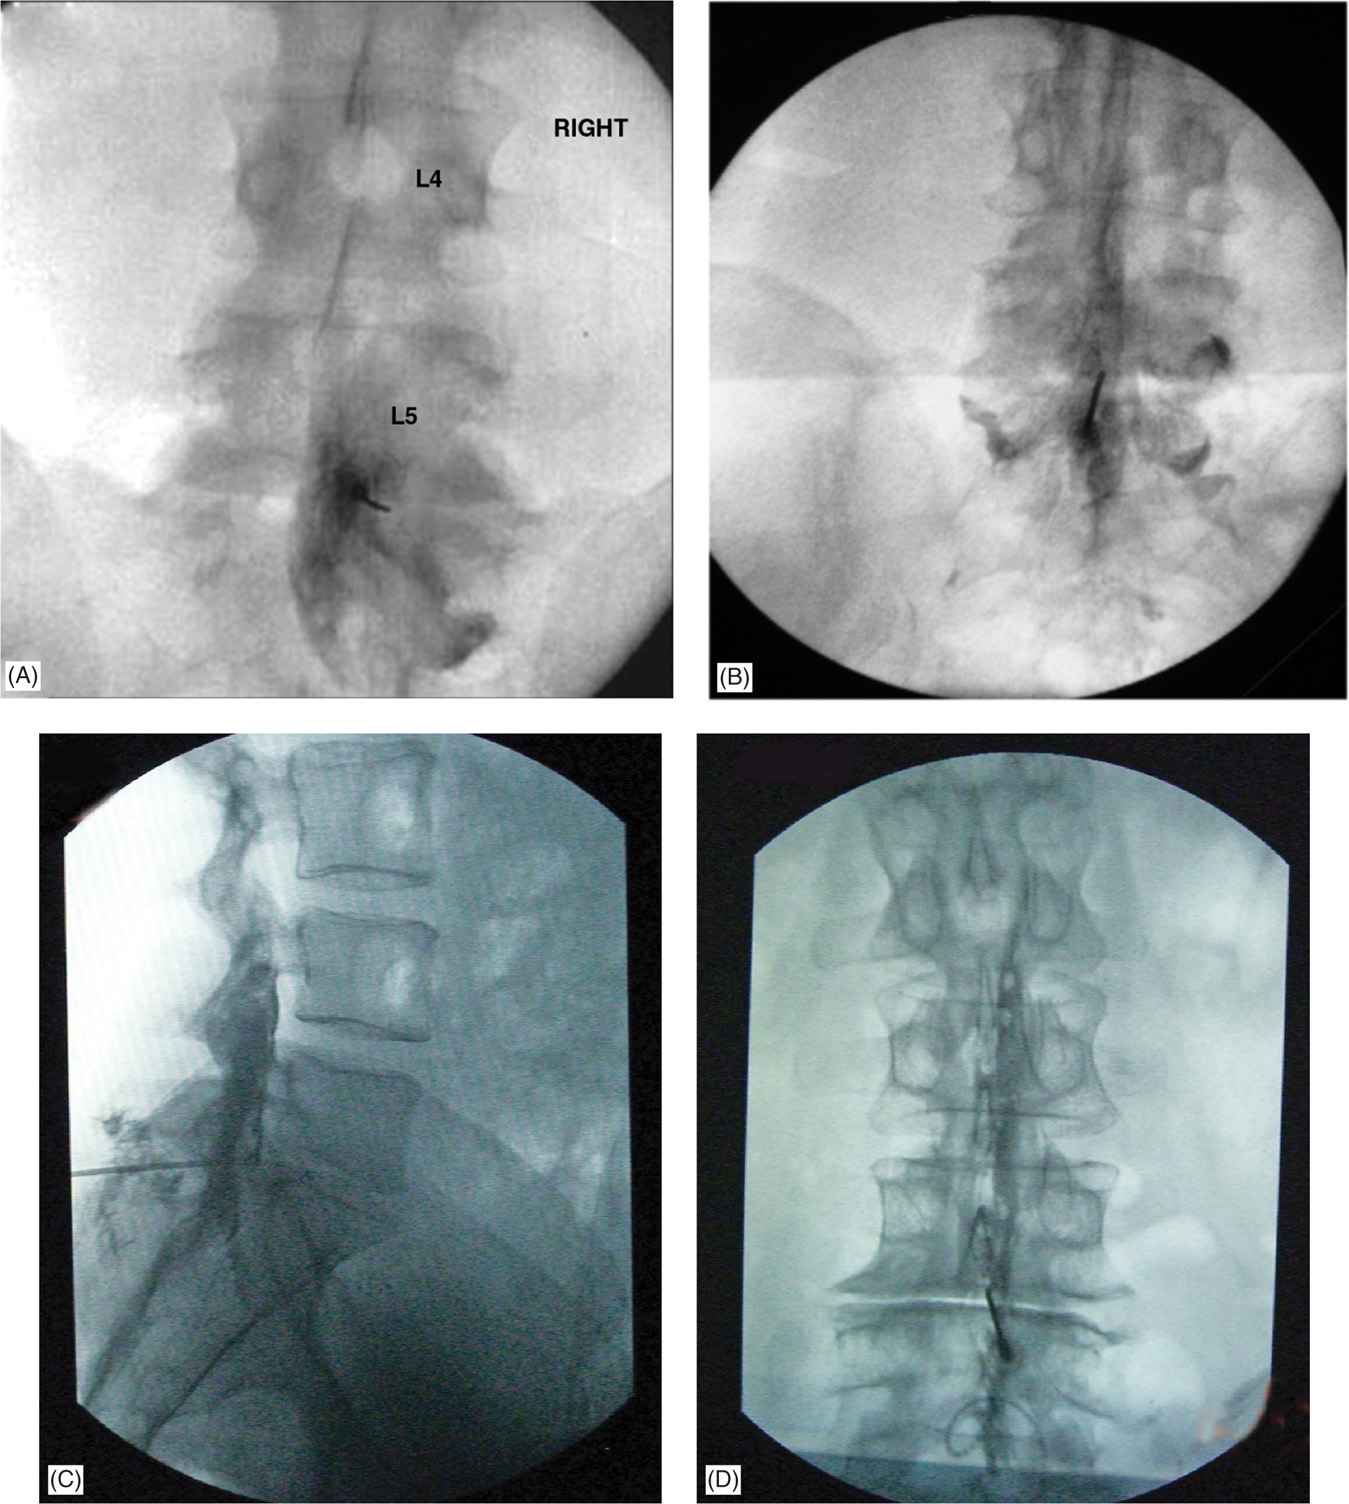

Fluoroscopic Guided Thoracic/Lumbar Interlaminar Epidural Steroid Lumbar Epidural Steroid Injection Help Epidural steroid injections may help relieve pain stemming from conditions such as spinal stenosis, foraminal stenosis, disc herniation, or degenerative disc disease. When administered in the lumbar epidural space, steroid injections may have the following benefits: A lumbar epidural steroid injection can relieve pain in your lower back or legs caused by inflammation of the nerves in your spine that.. Lumbar Epidural Steroid Injection Help.

Interlaminar Epidural Steroid Injections Cervical, Thoracic, Lumbar Lumbar Epidural Steroid Injection Help When administered in the lumbar epidural space, steroid injections may have the following benefits: A lumbar epidural steroid injection can relieve pain in your lower back or legs caused by inflammation of the nerves in your spine that. Healthcare providers use epidural steroid injections (esis) as a therapy option for certain causes of chronic pain. Epidural steroid injections may help. Lumbar Epidural Steroid Injection Help.